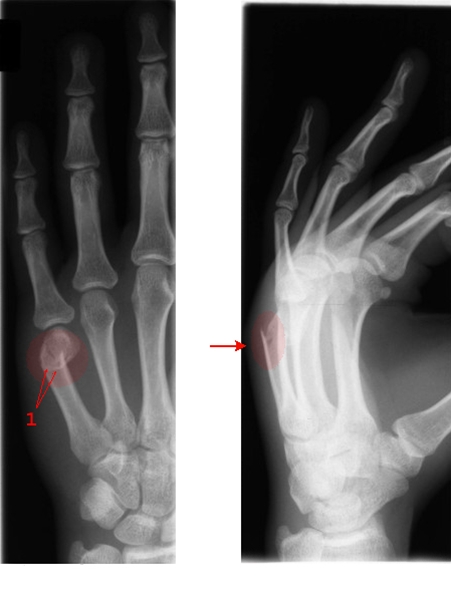

Tværbrud af femte mellemhåndsknogle (metakarp) ved knoen (pil). Typisk brud efter slag mod hårdt objekt og kaldes i engelsksproget litteratur "Boxer's fracture", da den typisk kan opstå ved slag med knytnæve. Ved brud på mellemhåndsknoglen vil der være smerter ved brug af hånden, ømhed ved tryk mod knoglen og eventuelt hævelse og misfarvning af huden.